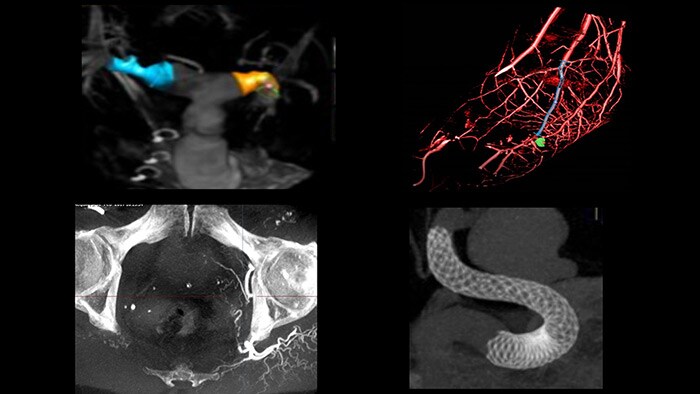

Ofrecemos una gama de herramientas clínicas avanzadas, como VesselNavigator, EchoNavigator y HeartNavigator para la orientación por imágenes 3D en vivo. Nuestra exclusiva Dynamic Coronary Roadmap (hoja de ruta coronaria dinámica) le ayuda a navegar por las arterias tortuosas de manera eficiente y precisa. Cada disciplina quirúrgica puede beneficiarse de herramientas avanzadas de fusión de imágenes que pueden mejorar la confianza, la eficiencia y la precisión durante los procedimientos.

SmartCT* le proporciona imágenes similares a las de la TC lo que le permite hacer mediciones y visualizaciones avanzadas en la pantalla táctil en la mesa, para estudiar el tipo y la extensión de la enfermedad con gran detalle. Las imágenes 3D de SmartCT* pueden ayudar a revelar información no aparente en las imágenes 2D o de la DSA. Esta información adicional puede cambiar el diagnóstico, la planificación del tratamiento o la administración del tratamiento, lo que respalda un mejor resultado para el paciente.17-19

En el laboratorio integrado de Azurion, los equipos de radiología intervencionista pueden acceder fácilmente a la medición y visualización 3D avanzadas de SmartCT, y a la imagenología intravascular (IVUS) de IntraSight en una pantalla táctil en la mesa para ahorrar tiempo y mejorar la confianza clínica.

El módulo de pantalla táctil (TSM) mejorado le permite controlar, de manera fluida, una amplia gama de herramientas de intervención multimodal, incluida la visualización y medición 3D avanzadas de SmartCT, el ultrasonido intravascular (IVUS) digital de instalación automática de IntraSight y otras herramientas compatibles de procedimientos específicos dentro del campo estéril. Esto reduce las interacciones y la necesidad de caminar de un lado a otro entre las diferentes consolas y la sala de control, para iniciar una aplicación o realizar una medición durante los procedimientos de radiología intervencionista.